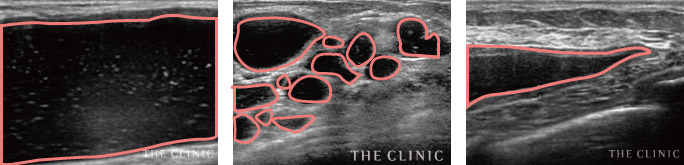

巨大なしこり

徐々に吸収されてなくなるはずのヒアルロン酸ですが、非常に大きなしこりが形成されてしまうこともあります。こちらは両胸ともに8cm以上のしこりが確認された症例です。

しこりの多発

しこり多発の原因は定かではありませんが、注入回数や体の中で流れることもあるヒアルロン酸の性質との関係性が考えられます。この症例もヒアルロン酸を繰り返し注入した方でした。

炎症

豊胸ヒアルロン酸注入が原因で、炎症を起こすこともあります。炎症が強くなると、皮膚の赤みや痛みを伴います。また、大胸筋内で生じた場合、腕が上がらないという機能障害に至ることも。

瘢痕

強い炎症で厚い被膜が形成され、瘢痕化したケースです。瘢痕化した場合、ヒアルロン酸がほとんど残っていないため、溶解注射の適応外。治療方法は切開除去のみとなります。